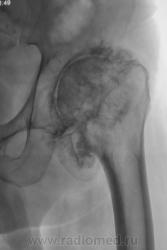

И вторичные выраженные деформирующие изменения на фоне двусторонней дисплазии суставов. Хондроматоз суставов

Наверное, в основе дисплазия (никогда такой не видел), но и об остеоартропатии мысль есть. Предполагаю заболевание спинного мозга.

Пациент в течение 3 лет самостоятельно не передвигается, основное положение - лежа.

сирингомиелия?

Наиболее вероятен диспластический генез коксартроза.

Последствия болезни Пертеса?